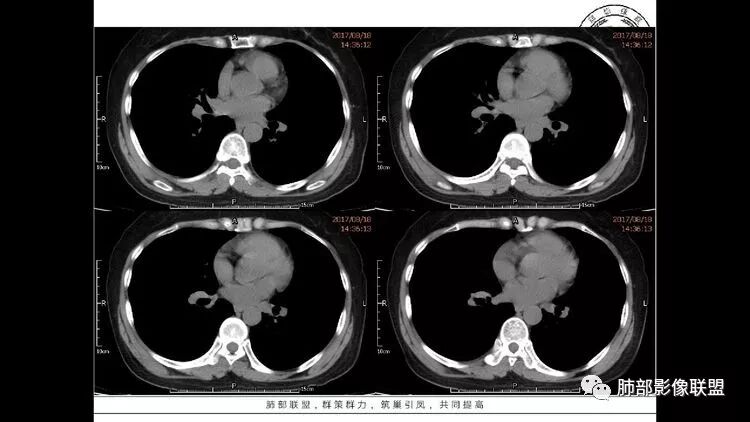

患者中年女性,因右眼红痛1天就诊。胸CT:双肺多发囊性变及结节影,囊以中下肺为多,部分囊内可见分隔及肺动脉,结节部分为实性,部分为混合性,边缘光滑,未见明显毛刺、棘突、胸膜牵拉及血管集束征象。双中下可见支气管扩张及树丫征。淋巴结无明显肿大。综合考虑:一元淋巴细胞间质性肺炎。多元鉴别肺腺癌并转移等恶性病变。

中年女性,因“角膜炎”入院,自用眼液2年,(眼干?)肺部:双肺多发类圆形薄壁气囊+实性结节+GGO,下肺分布为主,纵隔淋巴结肿大,考虑淋巴系统增殖,LIP可能性大,可能继发于干燥综合症;左肺下叶的混合磨玻璃结节形迹可疑,边界清晰,内部疑似空泡,扩张扭曲支气管,极像肺癌,伴双肺转移?待排吧

55岁女性,右眼红痛视力下降1天。既往有类风湿病史。两肺多发大小不等囊及结节,左下肺磨玻璃结节样病灶,纵隔占位。一元解释不了这么多不同病灶,二元甚至三元。纵隔恶性肿瘤并肺内转移?左下肺腺癌并肺内纵隔淋巴结转移?LIP?

多发气囊,气囊内可见血管进入,因患者眼干伴类风湿,可能有干燥综合征,那LIP可能性大。因为不是育龄期发病,可排除LAM。患者左纵膈淋巴结肿大,且有融合趋势,结合左下肺病灶,考虑合并恶性肿瘤,淋巴瘤?鉴别结节病

左肺下叶混杂密度病灶,其内可见空泡,周围ggo清楚,考虑浸润性腺癌。双肺散在多发薄壁囊腔和实性结节,以胸膜下及血管旁分布位于,气囊可见血管贴边征,双肺小叶间隔及中央间质增厚,局部可见磨玻璃影及树芽征,纵隔内淋巴结肿大,考虑LIP

综上,考虑左下肺浸润性腺癌+LIP

双肺多发大小不等囊腔,可见薄壁,部分囊腔内可见血管影,伴双肺多发结节,结合患者眼病及类风湿病史,考虑LIP可能大。另左肺下叶磨玻璃结节,边界清晰,内可见空泡,伴纵膈多发肿大淋巴结,不除外浸润性腺癌可能。

双肺多发散在斑片状磨玻璃密度影及大小不等的薄壁含气囊腔,下肺相对较多较大。双肺多发结节,界清,边缘光滑,分叶不明显。右肺下叶前外基底段散在斑片树芽。前上纵膈偏左侧不规则软组织团块,密度不均,其内可见不规则纤维样低密度,周围簇状小淋巴结。考虑1淋巴细胞间质性肺炎。2考虑纵膈胸腺淋巴瘤。